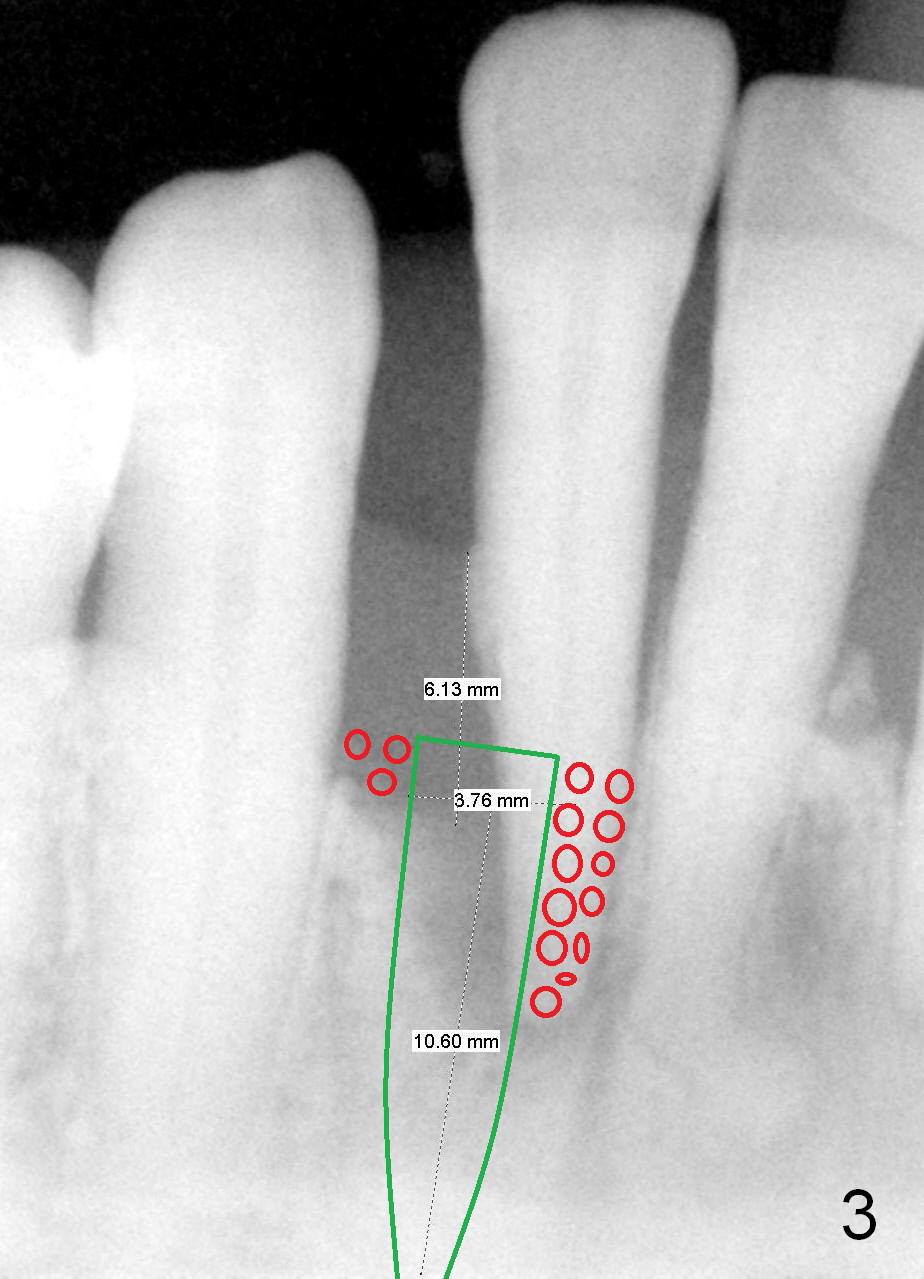

A tentative design is as follows: a bone-level implant is placed 4 mm subgingival (Fig.3, total gingival height 6 mm (Fig.2)). The cuff will be 4 mm. The most coronal threads are covered by bone graft (red circles).

If the patient turns out to be small in statue, crest width is narrow (by using bone caliper), and/or pilot drills are placed too buccal or lingual, a smaller 1 piece implant is to be chosen (2.5 mm). The lower incisor is the smallest tooth in the mouth. The small implant should sustain mastication.

The length of the implant will be 12 or 14 mm according to the new PA. Is 2.5 mm 1 piece implant indicated for this case? Return to Professionals, Lower Incisor Immediate Implant, Systemic Disease Xin Wei, DDS, PhD, MS 1st edition 03/09/2015, last revision 05/30/2018